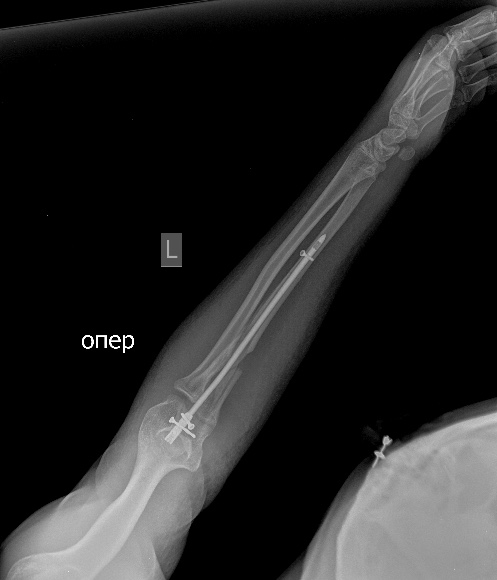

псевдоартроз локтевой с застарелым вывихом радиоульнарного сочленения |

Оперирована около 1 года назад. Радиоульнарное сочленение было вправлено, фиксировано спмцей, спица удалена. На сегодня имеем такую картинку. Работает водителем трамвая.Что посоветуете в этом случае? Восстановить длину локтя - это понятно. как лучше поступить с радиоульнарным сочленением?

Возможно, и поменяет. Позволит оценить некоторые аспекты. Характер псевдоартроза, смещения и т.д. Вообще, как-то странновато - ложный сустав, два вывиха на одном сегменте и снимок в одной проекции?! Поскольку второй проекции дождаться не удалось, предложу следующий план решения проблемы: Удаление пластины, остеосинтез аппаратом, постепенная дистракция, чрезочаговая репозиция спицами с упорами оставшихся смещений. Дёшево и эффективно. Вторая проекция помогла бы детализировать некоторые моменты. Ниже очень похожий случай, пациент оперирован через 8 месяцев после травмы.

Мы бы удалили пластину. Аппаратом постепенно восстановили бы взаимоотношения. И заштифтовали бы локтевую кость, смоделировав стержень, чтобы он был напряжен в противоположную сторону тому, как сейчас выглядит локтевая кость, т.е. вогнутой стороной в сторону межкостного промежутка. Чтобы лучевая кость удерживалась натяжением межкостной мембраны. Пример в приложении. Тут был более свежий случай, поэтому вправилось одномоментно.